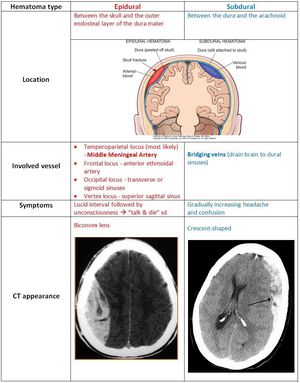

Hematoma

Epidural

Subdural